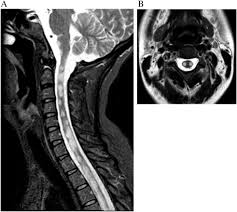

Guillain Barre Syndrome Spine Mri Of A 38 Year Old Iranian Female With Download Scientific Diagram

Guillain Barre Syndrome Spine Mri Of A 38 Year Old Iranian Female With Download Scientific Diagram from www.researchgate.net

Its signs and symptoms are similar to those of other neurological disorders and may vary from person to person. Sagittal and axial post contrast t1 fs images shows smooth thickening and abnormal enhancement of the cauda equina and the ventral nerve roots. Mri is sensitive, but nonspecific, for diagnosis. The diagnosis is usually established on the basis of symptoms and signs, aided by cerebrospinal fluid findings and electrophysiologic criteria. Clinical presentation is usually characterized by rapidly progressive, ascending, and symmetric paralysis of the extremities. Scott olson / staff / getty images Your doctor is likely to start with a medical history and thorough physical examination. It is the most common cause of rapidly progressive flaccid paralysis.

On csf analysis, the cell count is normal in 85% of patients, and high protein values are seen in 64%. Sagittal and axial post contrast t1 fs images shows smooth thickening and abnormal enhancement of the cauda equina and the ventral nerve roots. Clinical presentation is usually characterized by rapidly progressive, ascending, and symmetric paralysis of the extremities. Fisher syndrome, a clinical variant of guillain­ barre syndrome characterized by ataxia, are­ flexia, and ophthalmoplegia, brain stem lesions have been described with cranial mr.imaging (8). Typically, both sides of the body are involved, and the initial symptoms are changes in sensation or pain often in the back along with muscle weakness, beginning in the feet and hands, often spreading to the arms and upper body. Mr imaging findings in eight patients (three male, five female; With treatment, people may improve more quickly. However, it can reveal nerve root enhancement and may be an effective diagnostic adjunct. Your doctor may then recommend: The most common result is a weakness and numbness that starts at the tips of the fingers and toes and spreads inward toward the body. Moreover, gbs is also associated with any vaccination. Mri is sensitive, but nonspecific, for diagnosis. Immune checkpoint inhibitors (icis) have been increasingly used in the treatment of various types of tumors with favorable results.